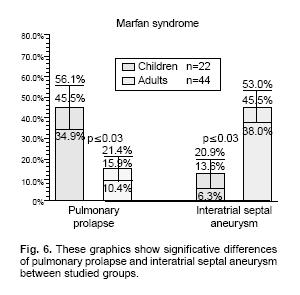

Results: Mean significant values between group I (children) and Group II (adults) were as follows: aortic annulus 16.62 ± 4.57 mm/m2 vs 12.81 ± 1.95 (p< 0.001), aortic root 23.30 ±7.49 mm/m2vs 18.36 ± 2.97 (p < 0.001), sinuses of Valsalva 24.14 ± 7.29 mm/m2 vs 19.84 ± 3.59 (p < 0.001), ascending aorta 18.43 ± 5.90 mm/m2 vs 17.02 ± 4.79 (p < 0.001), aortic arch 16.12 ± 4.73 mm/m2 vs 14.20 ± 2.68 (p < 0.001). Pulmonary valve prolapse was seen in 10/22 (45.5%) vs 7/44 (15.9%), p < 0.03. Interatrial septal aneurysm was found in 3/22 (13.6%) vs 20/44 (45.5%), p < 0.03. There was a significative diference in the presence of atrial septal aneurysm between the adult group and control group (p < 0.001).

Conclusions: The incidence of cardiovascular abnormalities in our series is similar to that in the literature with the exception of the very high incidence of pulmonary valve prolapse vs control groups, then it suggests that the clinical manifestations of MFS are strikingly severe in the Mexican population. Also a high incidence of interatrial septal aneurysm (34.9%) in comparison to control groups (18.2%) was found.

Mitral valve prolapse was found in 21 patients (95.5%) of Group I and in 32 (72.7%) of Group II (p = ns, Figs. 2a, b). Tricuspid valve prolapse was detected in 18 (81.8%) patients of Group I and in 26 (59.1%) of those in Group II (p = ns, Fig. 3). Aortic valve prolapse was found in 5 patients (22.7%) of Group I and in 5 (11.4%) of Group II (p = ns, Figs. 4a, b). Furthermore, pulmonary valve prolapse was found in 10 patients (45.5%) of Group I and in 7 (15.9%) of Group II (p <0.03, Table IV, Figs. 5a, b). In contrast, mitral, tricuspid, aortic and pulmonary valve prolapse was not observed in both control groups (p < 0.001) (Fig. 6).

Forty–two patients (63%) had lesions in two or more heart valves, 15 (22.7%) in a single valve, and in 9 (13.6%) no valve lesion was found. Interatrial septal aneurysm was found in 23 patients (34.9%). In 12 of these, bulging of the septum was to the right, in 7 towards the left, and in both directions in 4 instances. Three of the patients with interatrial septal aneurysm pertained to Group I (13.6%) vs 3 of control I (27.2%) and 20 patients to Group II (45.5%) vs 3 of control II (13.6%), (Fig. 7), with a significative difference between these last both (p < 0.001). Interatrial septal aneurysm coexisted with mitral valve prolapse in 21 cases (21/23, 91%). In one case, from Group II interatrial septal aneurysm was associated with a ischemic cerebral vascular event, (Table IV).

In two series of MFS patients, mitral valve prolapse has been found in up to 80% of cases. This percentage is in agreement with our findings of mitral valve prolapse in 80.3%.13,14 The mitral was the most commonly affected heart valve, followed by the tricuspid and pulmonary valves. In this cohorts there was a sizable percent of cases (21.2%) with pulmonary valve prolapse in association with pulmonary regurgitation, which was significantly more frequent in Group I (p = 0.006) when it was compared with control groups. Recent surgical and pathologic studies have demonstrated myxomatous degeneration of aortic, tricuspid and mitral valves. At present, prognostic implications of isolated pulmonary valve prolapse or in association with pulmonary valve regurgitation have not been explored in Marfan syndrome. Since the pulmonary valve is made up of essentially the same tissue as the aortic valve, it would be reasonable to assume that both valves could be equally affected in patients with Marfan syndrome. Moreover, it has been suggested that the abnormalities are not confined to a single valve but may involve all of the endocardial tissue, leading to multivalvular compromise. Indeed, in our series 63% of patients had involvement of two or more heart valves.

This is the first report of a large number of interatrial septal aneurysm in patients with Marfan syndrome, with a frequency of 34.8% in our series, and 7.6% of these had cerebral ischemic events. In the majority (31.8%), interatrial septal aneurysm coexisted with mitral valve prolapse but never with patent foramen ovale. Isolated interatrial septal aneurysm or interatrial septal aneurysm associated with mitral valve prolapse was significantly more common in adults than in children, p < 0.03 and p < 0.05, respectively. This suggests that in Marfan syndrome the connective tissue abnormality also involves the interatrial septum. The prognostic significance of interatrial septal aneurysm in Marfan syndrome is yet to be determined. Furthermore interatrial septal aneurysm has been shown to be a major source of thrombi, and when it occurs concomitantly with mitral valve prolapse it could potentiate the cardioembolic risk as was previously described.20

The incidence of cardiovascular abnormalities in our series is similar to that in the literature with the exception of the very high incidence of pulmonary valve prolapse in relation to control groups (0%), it suggests that the clinical manifestations of Marfan syndrome are strikingly severe in the Mexican population. Our patients also had a high incidence of interatrial septal aneurysm (34.9%) vs control groups (18.2%). Only isolated cases associated with Marfan syndrome have been reported heretofore. The measurements of segments of the aorta should be corrected to body surface area, as they are different in children and adults.